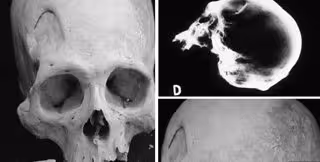

Los expertos explican que los esqueletos de la región han puesto de manifiesto la violencia que protagonizaba esta población: como huesos rotos o cráneos con agujeros. Pero también se pueden ver marcas que sugieren que esta antigua cultura realizaba cirugía craneal en un intento por salvar vidas.

Los cráneos incluso revelan pistas sobre cómo estas técnicas rudimentarias evolucionaron con el tiempo hasta tener una mayor tasa de éxito.

El equipo se centró en la práctica de la trepanación en la región a partir de cráneos recogidos en yacimientos de la zona del Titicaca. Esta práctica es una antigua forma de cirugía craneal, que fue utilizada para fines médicos y rituales. En ese momento había varios tipos de trepanación: raspado de cráneo, cortes lineales y ranura circular.

Estudios elaborados sobre momias peruanas insinúan que se usaban herramientas de metal en los procedimientos y se colocaban placas sobre el agujero después, aunque, según los expertos, nos se ha encontrado evidencias de estos sucesos en los nuevos cráneos.